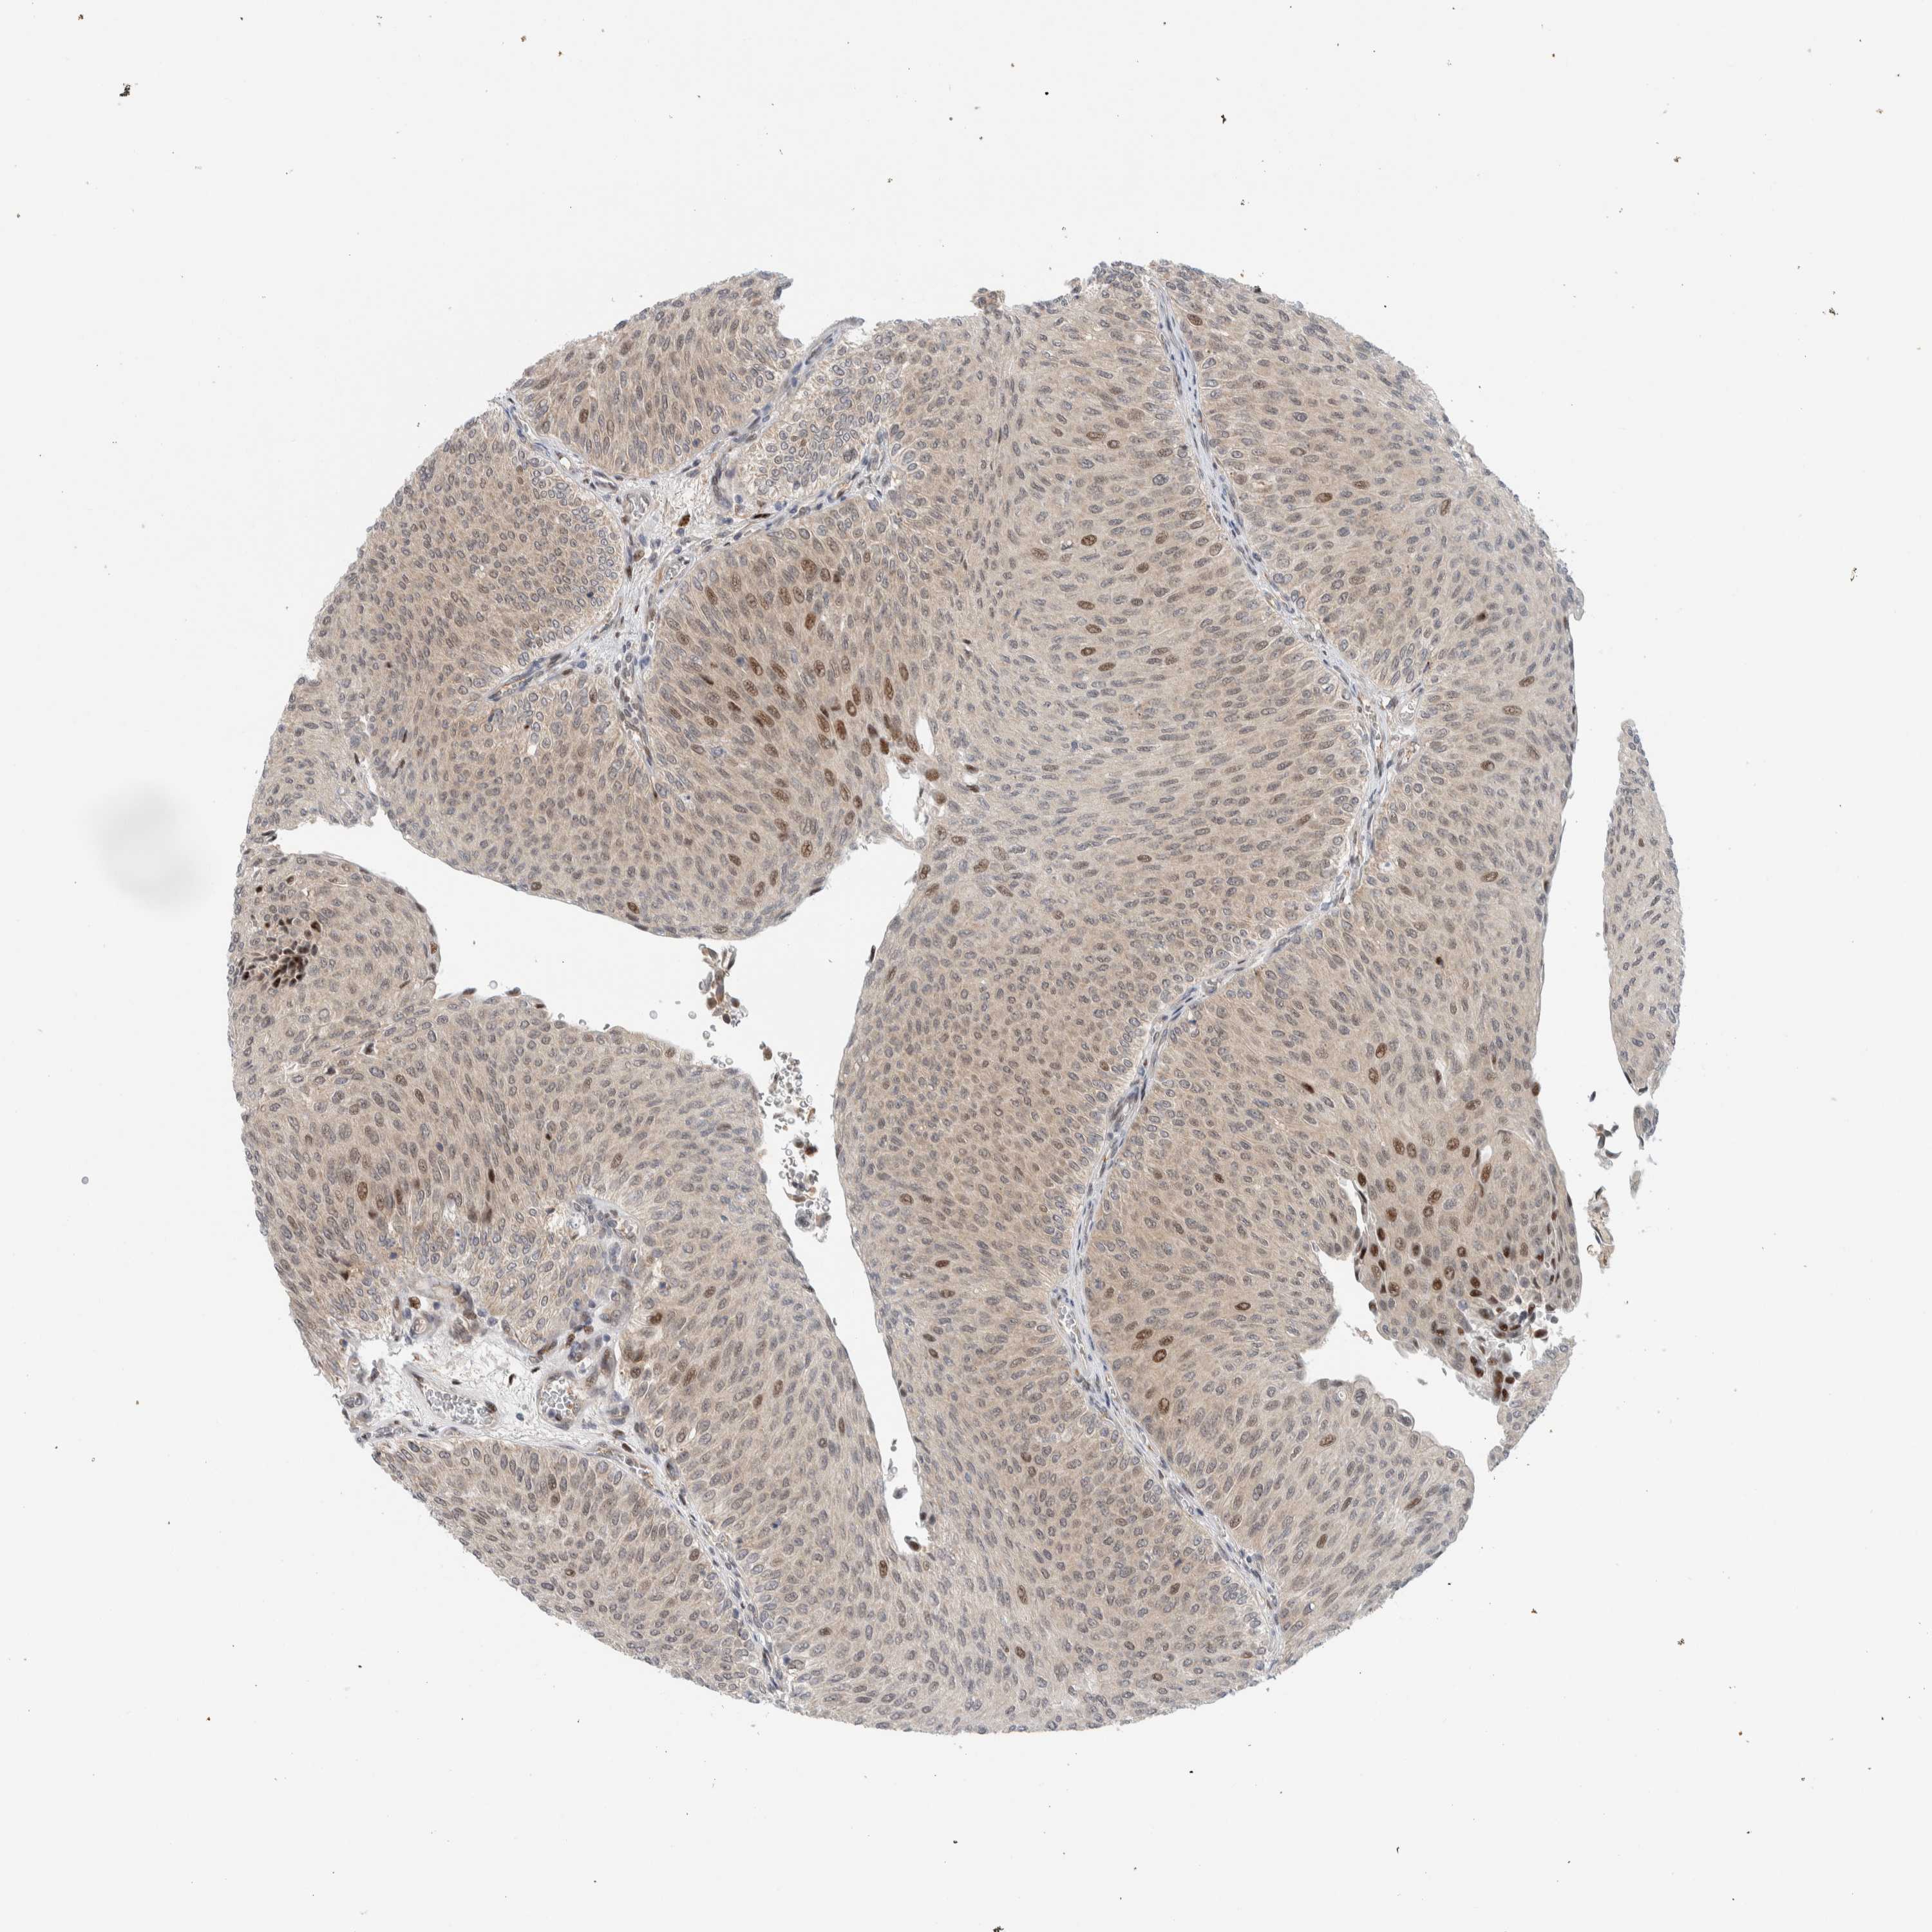

UROTHELIAL CANCER - Protein expressioni

A mouse-over function shows sample information and annotation data. Click on an image to view it in a full screen mode. Samples can be filtered based on level of antibody staining by selecting one or several of the following categories: high, medium, low and not detected. The assay and annotation is described here.

Antibody stainingi

Antibody staining in the annotated cell types in the current human tissue is reported as not detected, low, medium, or high, based on conventional immunohistochemistry profiling in selected tissues. This score is based on the combination of the staining intensity and fraction of stained cells.

Each image is clickable and will lead to virtual microscopy that enables deeper exploration of all samples and also displays staining intensity scores, fraction scores and subcellular localization as well as patient and tissue information for each sample.

Antibody HPA024137

Staining

High

Medium

Low

Not detected

Intensity

Strong

Moderate

Weak

Negative

Quantity

>75%

75%-25%

<25%

None

Location

Nuclear

Cytoplasmic/membranous

Cytoplasmic/membranous,nuclear

Urothelial carcinoma, Low grade

Urothelial carcinoma, High grade